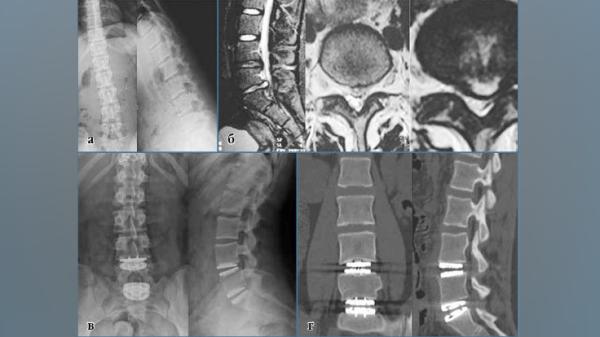

В рамках конференции с докладом выступил травматолог-ортопед Национального центра травматологии и ортопедии Бактыбек Джалилов. Он представил участникам исследование на тему «Грыжа межпозвонкового диска у детей и подростков».

При отсутствии положительной динамики в течение 6 недель, а также при выраженном болевом синдроме и неврологических нарушениях, рекомендуется оперативное вмешательство. Среди современных методов хирургического лечения — микродискэктомия и эндопротезирование — которые зарекомендовали себя как безопасные и эффективные для детского возраста.